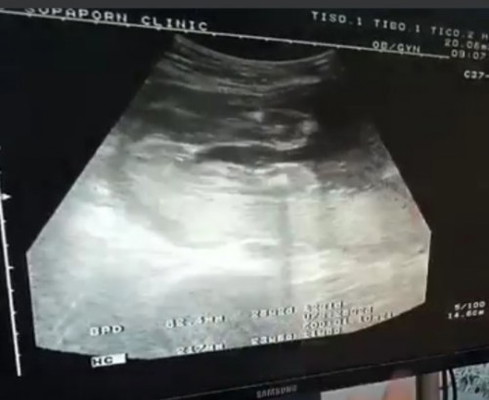

มีแต่คนทักว่าได้ลูกชาย เพราะโทรมสิวขึ้น คอดำ พอซาวด์หมอบอกผู้หญิง แม่ๆช่วยดูหน่อยจ้า

ผู้หญิงค่ะ เพราะไม่เห็นจู๋น้องโผล่ ลักษณะภายนอก การแพ้ท้อง ลักษณะท้อง หรือของที่อยากกิน เป็นที่ตัวเราล้วนๆค่ะ ไม่เกี่ยวกับเพศลูกจ้า เราผิวขาว หน้าใส คอกับรักแร้ไม่ดำ อยากกินแต่ของหวาน ยังได้ลูกชายเลยค่ะ